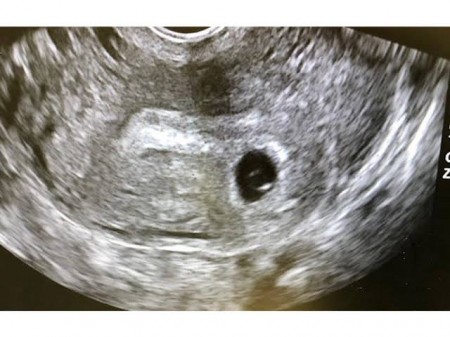

anne baba olmak isteyenlerin korkulu ruyasi bos gebelik hakkinda yeterince bilgiye sahip misiniz onedio com